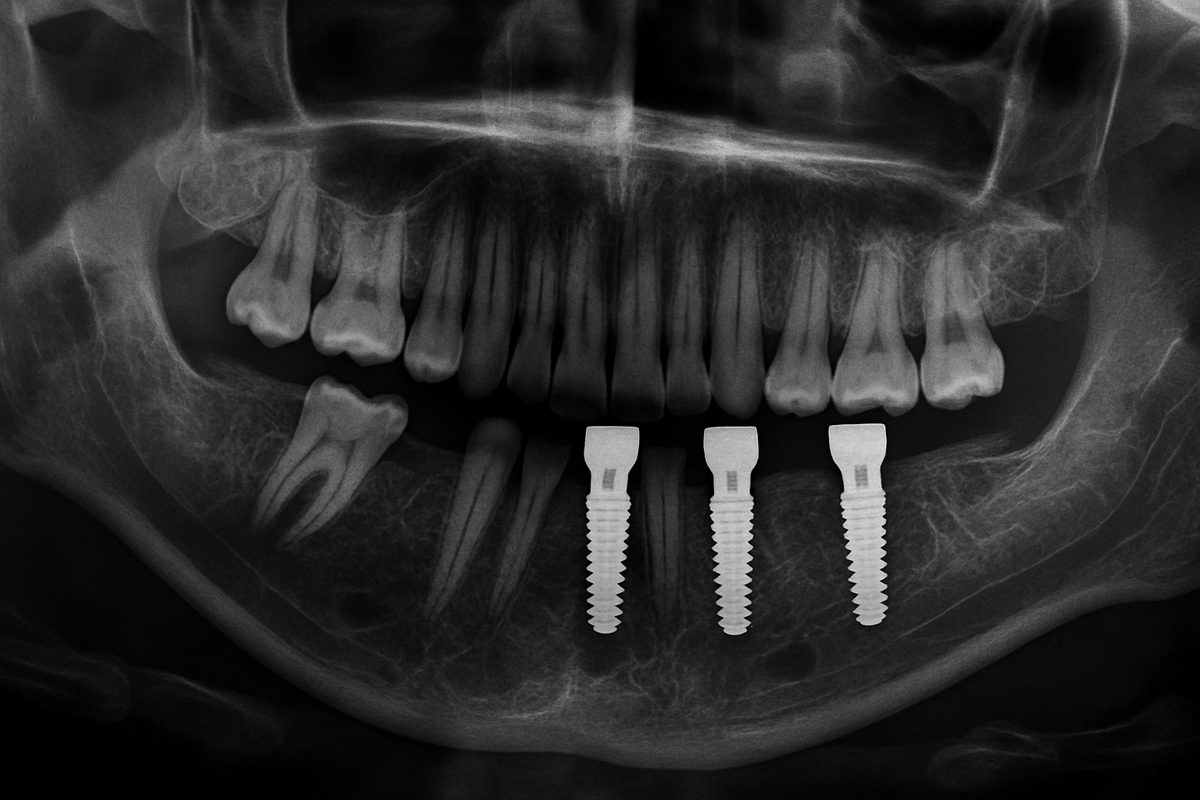

Tooth implants in, Hannibal, MO, might be the unsung heroes of dental implant procedures. These essential components, often made from titanium, support the replacement tooth or crown as an artificial tooth root. Being bio-friendly, these tooth posts seamlessly merge with your jawbone over time – a process known as osseointegration, providing sturdy support and stability to the dental implant, just like your natural tooth root would.

Knowing the ‘what’ and ‘why’ of tooth posts, it’s important to understand the ‘how’. The process of tooth post-placement is simple and involves little to no discomfort. After a comprehensive dental examination and the required imaging, your oral surgeon gently embeds the tooth post into your jawbone. It’s then left to heal and integrate into your jawbone over a period of months. After successful osseointegration, the artificial crown is secured atop the tooth post.